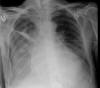

Neumonia basal derecha.

Neumonía basal derecha.